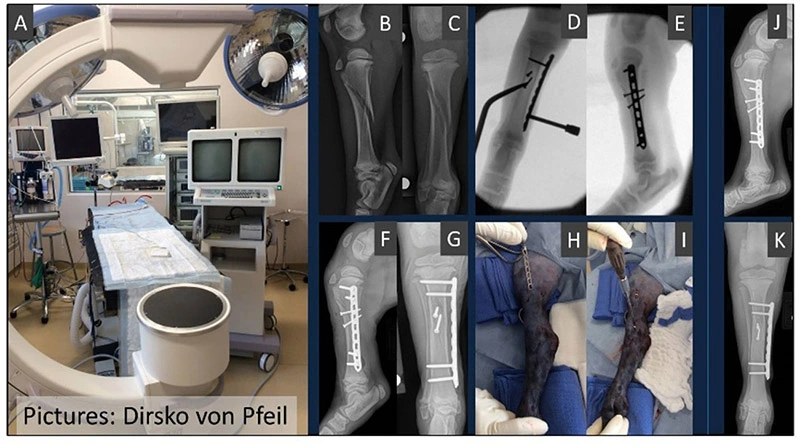

Frakturversorgung minimal-invasiv

Einsatz oft in Kombination mit einem hochmodernen C-Bogen (Fluoroskopie)

Wenn indiziert, kann minimal invasive orthopädische Frakturbehandlung weniger schmerzhaft und mit schnellerer Heilung als bei der klassischen Frakturversorgung verbunden sein.

Durchleuchtungsgerät im OP (A). Reparatur einer Fraktur unter fluoroskopischer Kontrolle mittels minimal-invasiver-Chirurgie (B-E: ursprüngliche Fraktur und Behandlung, F,G: nach der Operation). Beachten Sie die kleinen Hautschnitte (H,I) und die ausgezeichnete Heilung innerhalb von nur 4 Wochen (J,K). Die Operation durch einen zertifizierten Orthopäden führt in der Regel zu guter Heilung.